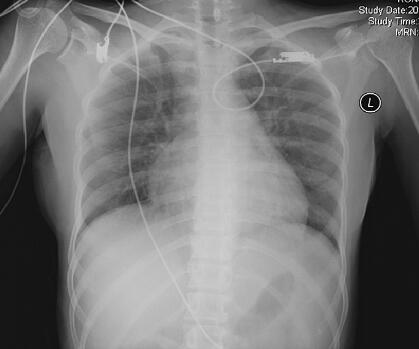

辅助检查:心电图:窦性心动过速,心率122次/分,V2~V6导联T波倒置。尿液分析:酮体1.5,比重≥1.030,蛋白1.0,潜血大量,白细胞(−),pH 6.0,胆红素阴性,尿胆原3.3μmol/L。全血细胞分析:WBC 4.32×109/L,N 87.4%,Hb 117g/L,PLT 106×109/L。心脏标志物:MYO>500ng/ml,CK-MB 22.2ng/ml,TnI<0.05ng/ml。心脏型脂肪酸结合蛋白阳性。DIC分析:PT 12.3秒,PTA 72.7%,INR 1.1,FIB 322.7mg/dl,APTT 38.4秒,FDP 5~20μg/ml,D-二聚体941.6ng/ml。生化检查:ALT 93U/L,AST 332U/L,LDH 1688U/L,TP 84.7g/L,CK 3549U/L,A/G 0.87。急诊生化检查:钠126.6mmol/L,氯103mmol/L,钾4.89mmol/L,BUN 5.8mmol/L,肌酐37μmol/L。胸片示双肺纹理增粗,心影饱满(图1)。床边腹部B超示肝胆胰脾肾未见异常。

图1 入院时胸片示双肺纹理增粗,心影饱满